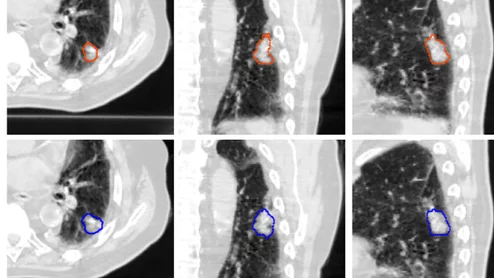

The influential task force dictates whether health insurers must cover preventive services such as mammograms and low-dose CT lung exams, which some say could be in jeopardy.